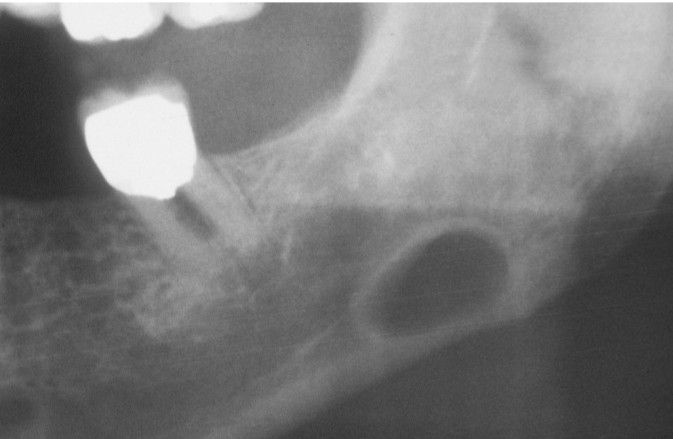

Stafne defect

Stafne Defect. Radiolucency of the posterior mandible below the mandibular canal.